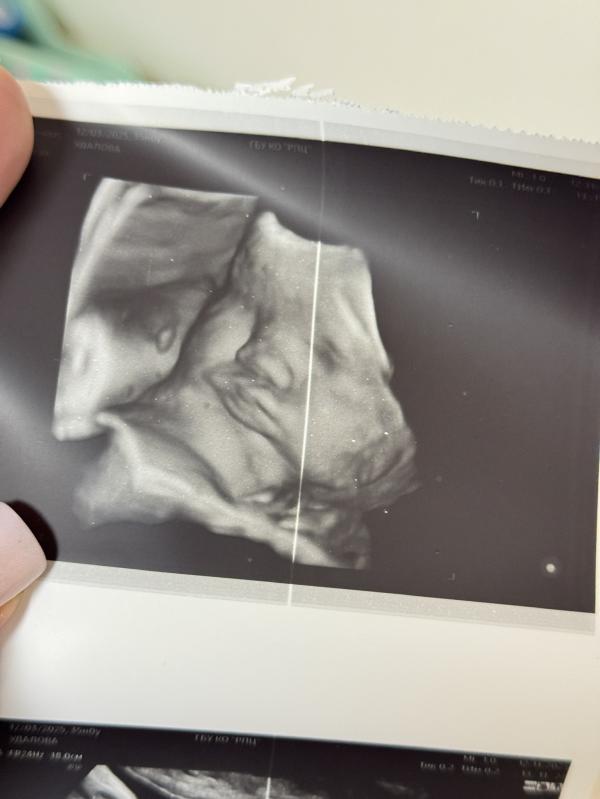

35 недель ровно прошли

Мы перевернулись , как надо 🙏🏽

Но вес этой дамочки пишут уже 3600 г🥴

Я не уверена что эти щеки пройдут 🤣